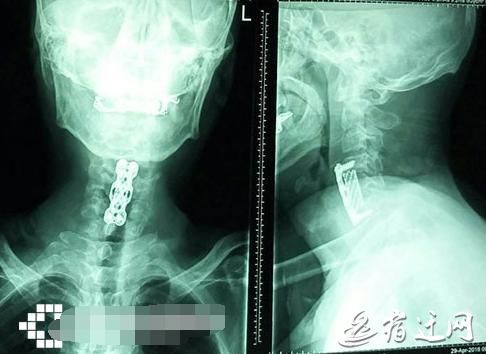

53岁大伯仰头喝可乐突然四肢瘫痪

“颈椎病是一个由量变到质变的过程。事后我们询问,他说自己早前就有脚麻、走路时脚踩棉花的感觉,这是脊髓型颈椎病的典型症状,但他一直没重视?!宾囊缴?。

经过治疗,王大伯的腿可以微微抬一抬了,但想要下地扶拐走路,还要等上半年。躺在病床上的王大伯感慨,“我再也不想喝可乐了?!?/p>

颈椎不适持续72小时应就医“王大伯的遭遇也提醒大家,平时要?;ぞ弊?,要少喝碳酸饮料?!宾囊缴?,尤其是躺在床上、坐公交车、吃饭前都喜欢掏出手机刷朋友圈的低头族,颈部肌肉力量长时间不平衡,会造成颈椎生物力学的改变。